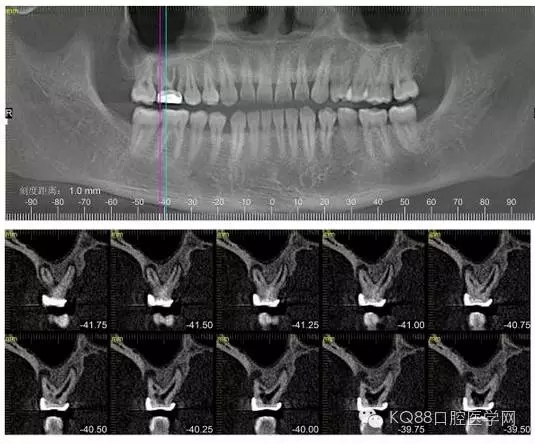

下面是拔牙前 CBCT

清晰可見根尖部陰影區(qū)域明顯。遠中頰根

近中頰跟,同時可以看出離上頜竇比較近,且伴有骨缺損。

這個切面可以看到根裂。